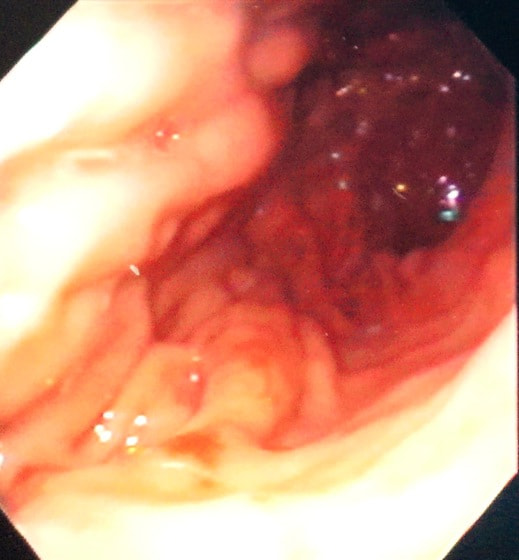

症例:炎症性ポリープ M.ダックス 10歳 オス

主訴:8ヶ月前から便が細くなり、血が混じることがある。その他、元気・食欲等、一般状態は良好。

経過:超音波検査にて直腸壁の肥厚(5㎜)が認められた。また、直腸検査で直腸全周に結節状病変を触知し、出血も確認された。消炎剤、抗生剤、整腸剤による治療への反応が長期的に悪いため、生検も含めた内視鏡検査を実施した。

内視鏡検査:肛門付近の直腸全周に、炎症および出血を伴う結節状病変を多数認めた。

病理検査:直腸の病変は、良性の非腫瘍性病変の一つである“炎症性ポリープ”と診断された。

診断後経過:炎症性ポリープは多発する傾向や腫瘍に転化する可能性があるため、消炎剤、抗生剤、整腸剤による内科療法を継続しながら、現在プルスルー法による外科的摘出術を検討中。